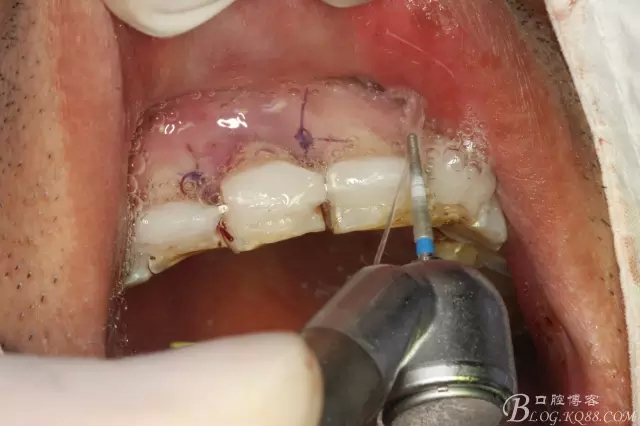

圖12.全酸蝕要粘結(jié)的牙面。并縫合11兩側(cè)牙齦。